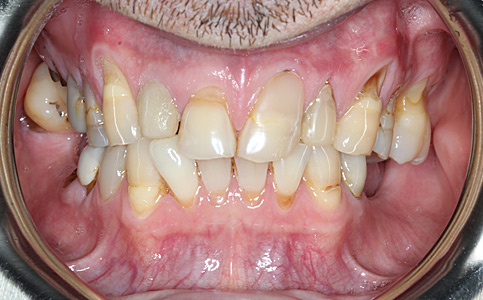

Przykład pełnej rehabilitacji protetycznej obejmujący leczenie biologiczne, uzupełnienie braków zębowych implantami oraz korony pełnoceramiczne w łuku górnym i dolnym. Spektakularna metamorfoza uśmiechu wykonana przez zespół Centrum Stomatologii i Ortodoncji FRESHmed odmieniła życie Pacjenta dodała pewności siebie i sprawiła, że z chęcią się uśmiecha.